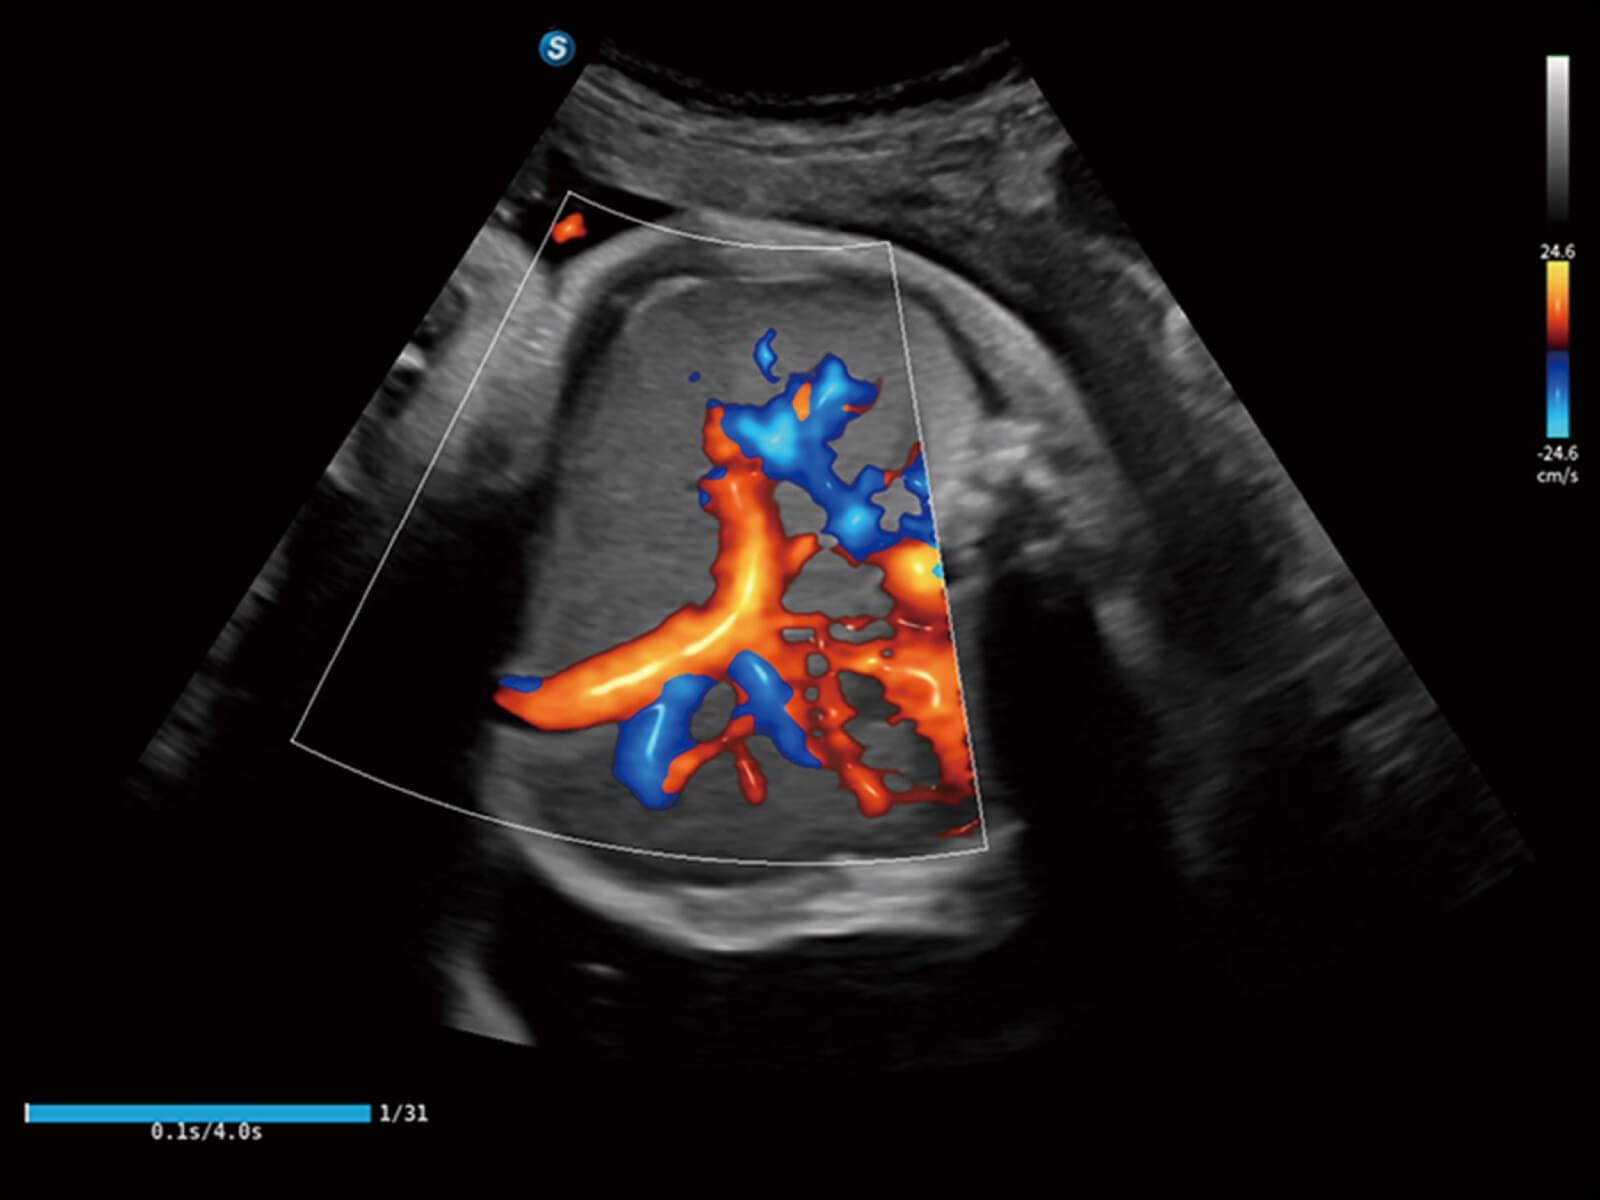

Bright Flow立体血流成像

通过光照模型,使二维血流显示出立体的效果,增加血流的敏感性、成束性,减少外溢。可以和其他不同的血流技术联合使用,轻松应对微小血管,增强血流的立体效果,提升视觉敏感性。

临床图

肝细胞癌立体血流